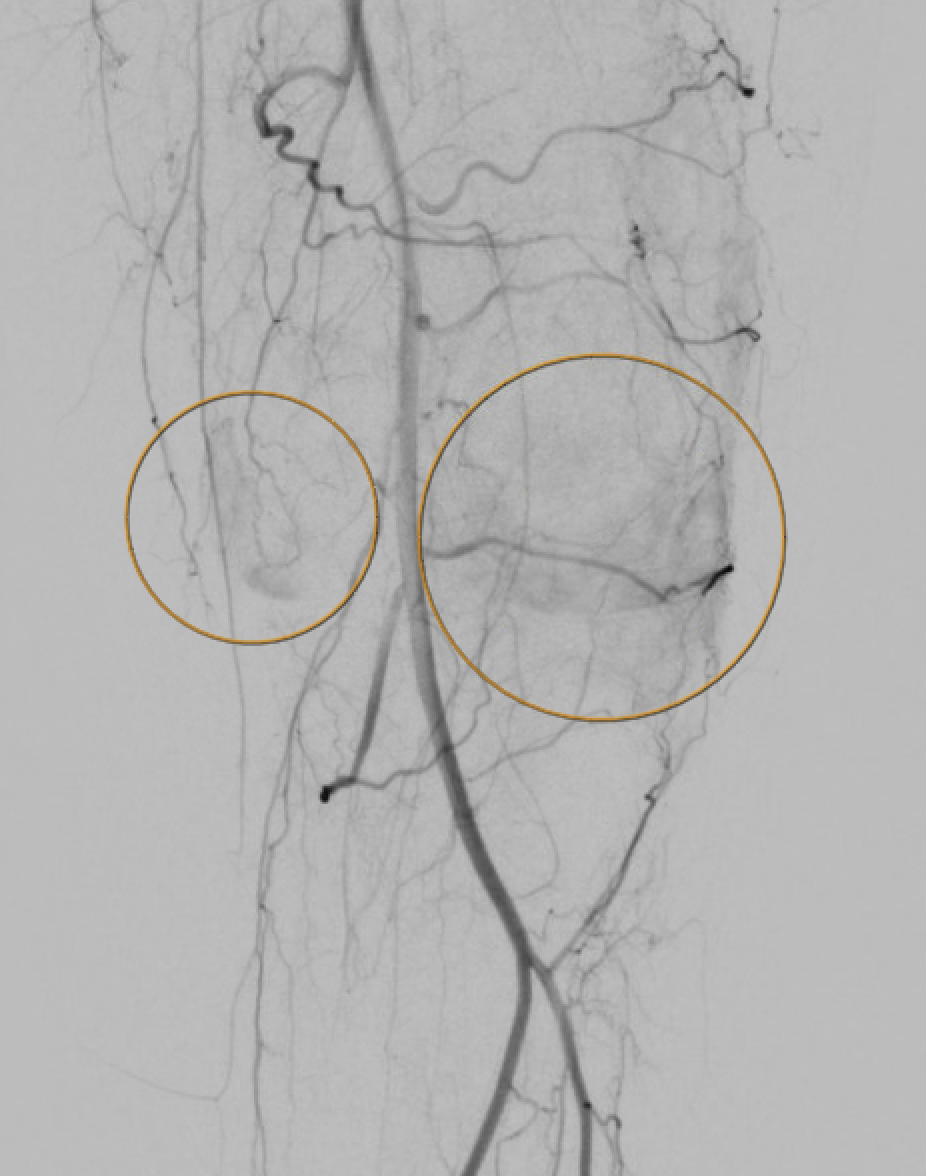

Knowledge of anastomoses is essential — non-target embolization to the saphenous branch of the DGA or cutaneous branches of the SMGA/SLGA is the most common source of complications.

Genicular artery anatomy — descending genicular (DGA) from the SFA and the superior/inferior medial and lateral genicular branches from the popliteal artery, forming the periarticular anastomosis of the knee.

Angiographic hyperemia / synovial blush in the symptomatic territory is the primary target. This appears as a late-phase parenchymal blush beyond the normal capsular stain.

Pre-embolization selective genicular angiogram demonstrating hypertrophied vessels and synovial hypervascularity in the territory of the patient's pain.Post-embolization angiogram showing pruning of the abnormal hypervascularity with preserved flow to normal tissue — the desired endpoint.